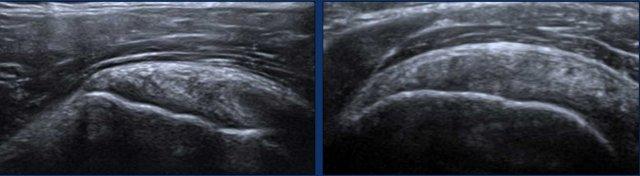

Intrasubstance tears

Rách nội chất là các vết rách một phần chiều dày không lan đến bề mặt khớp hoặc bề mặt túi hoạt dịch của gân.

Hình ảnh

Các hình ảnh minh họa hai ví dụ về rách nội chất nhỏ.